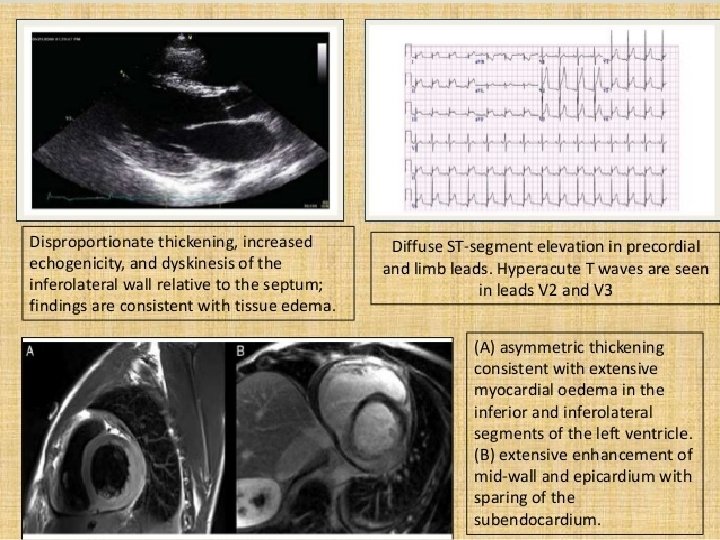

LAKE LOUISE CRITERIA In the setting of clinically suspected myocarditis, cardiac MRI fi ndings are consistent with myocardial infl ammation if at least 2 of the following criteria are present: 1. Regional or global myocardial signal intensity increase in T 2 -weighted images 2. Increased global myocardial early enhancement ratio between myocardium and skeletal muscle in gadolinium-enhanced T 1 -weighted images 3. There is at least 1 focal lesion with nonischemic regional distribution in inversion-recovery prepared gadolinium-enhanced T 1 -weighted images (delayed enhancement) Cardiac MRI study is consistent with myocyte injury or scar caused by myocardial inflammation (or both) if criterion 3 is present A second cardiac MRI study 1 to 2 weeks after the initial cardiac MRI study is recommended if either of the following is true: None of the criteria are present, but the onset of symptoms is very recent and there is strong clinical evidence for myocardial infl ammation One of the criteria is present The presence of left ventricular dysfunction or pericardial effusion provides additional, supportive evidence for myocarditis CMR